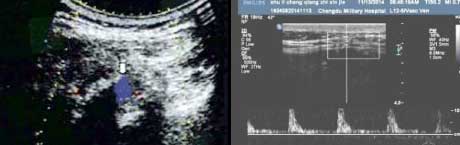

一、发现AS肌腱端炎改变,定性确诊疾病所属

肌腱端炎是AS的基本病理改变,但由于缺乏典型炎症表现(红、肿、热),临床很难早期诊断肌腱端炎。肌骨超声以其敏感度很高的非侵入性检查方法,可提供炎性肌腱异常血流动力学方面的信息,如血流方向、速度及阻力情况等,对血流信号进行定量分析,在强直早期精准判定肌腱炎存在。并通过观察肌腱是否增厚、回声强弱、肌腱周围组织水肿及滑膜肿胀程度,反映关节滑膜及肌腱的病理改变、提供AS炎症活动度评估病变,为患者早期治疗提供帮助。